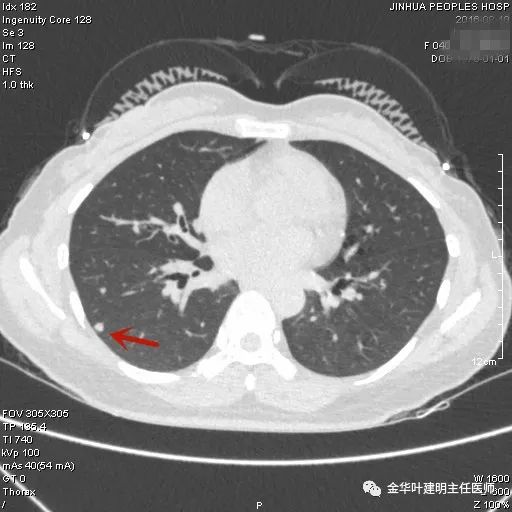

上图示隐球菌性结节。是典型的表现,高密度结节,周围部位,病灶有晕征,收缩力弱(邻近胸膜无牵拉凹陷)。